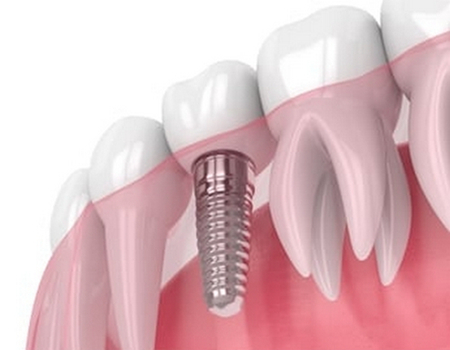

种植牙具有一定风险性,做种植牙很可能会出现植牙失败以及植牙感染等风险。因为种植牙手术是在牙龈以及牙槽骨之间种植金属螺钉或者是类似物做支撑的,螺钉很可能会出现断裂或者松动以及周围感染等情况,从而会导致种植牙失败。其次种植牙术后需要做相关护理,比如口腔清洁或者口腔卫生,如果术后没有做好伤口护理的话,很可能会使植入体感染,此后就会出现疼痛或者肿胀等不适情况严重的时候还需要做手术处理。

种植牙常见的后遗症就是骨质损伤或者神经损伤。因为做种植牙的时候,如果骨质受到太大压力的时候或者是由于牙槽膨胀而出现转移的时候以及牙齿种植体不稳当的时候,都会使骨质组织受到一定损伤。其次,由于种植牙需要对局部做切开处理,对附近血管和神经就会产生一定影响,一旦当神经系统受到损伤的时候,很可能后期会出现神经麻木或者感觉异常等情况。所以在做种植牙手术的时候,一定要做足充分攻略,要谨慎选择医院和医生,术后还要做好伤口部位的卫生护理。就能够很大程度避免这些后遗症。